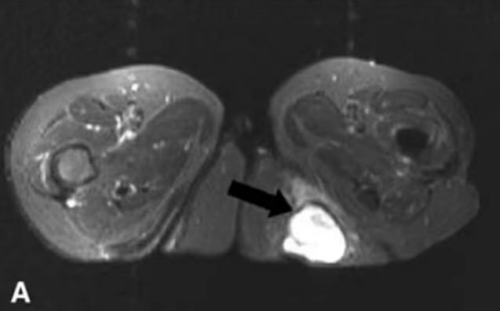

图中箭头所指为“坐骨结节囊肿”

李良军详细地向患者及家属讲解了这个疾病的由来及治疗方案,并安慰患者无需太过紧张,目前,通过关节镜微创手术治疗就可以为老奶奶解决这个“难言之痛”。经完善术前相关准备后,老人入院第二天便接受了微创手术治疗,手术切口仅为两个0.5cm大小的小孔,术后当天患者即可下床活动,术后第二天李奶奶便开心地出院了,出院时,不停地向李主任和医护人员连连道谢!